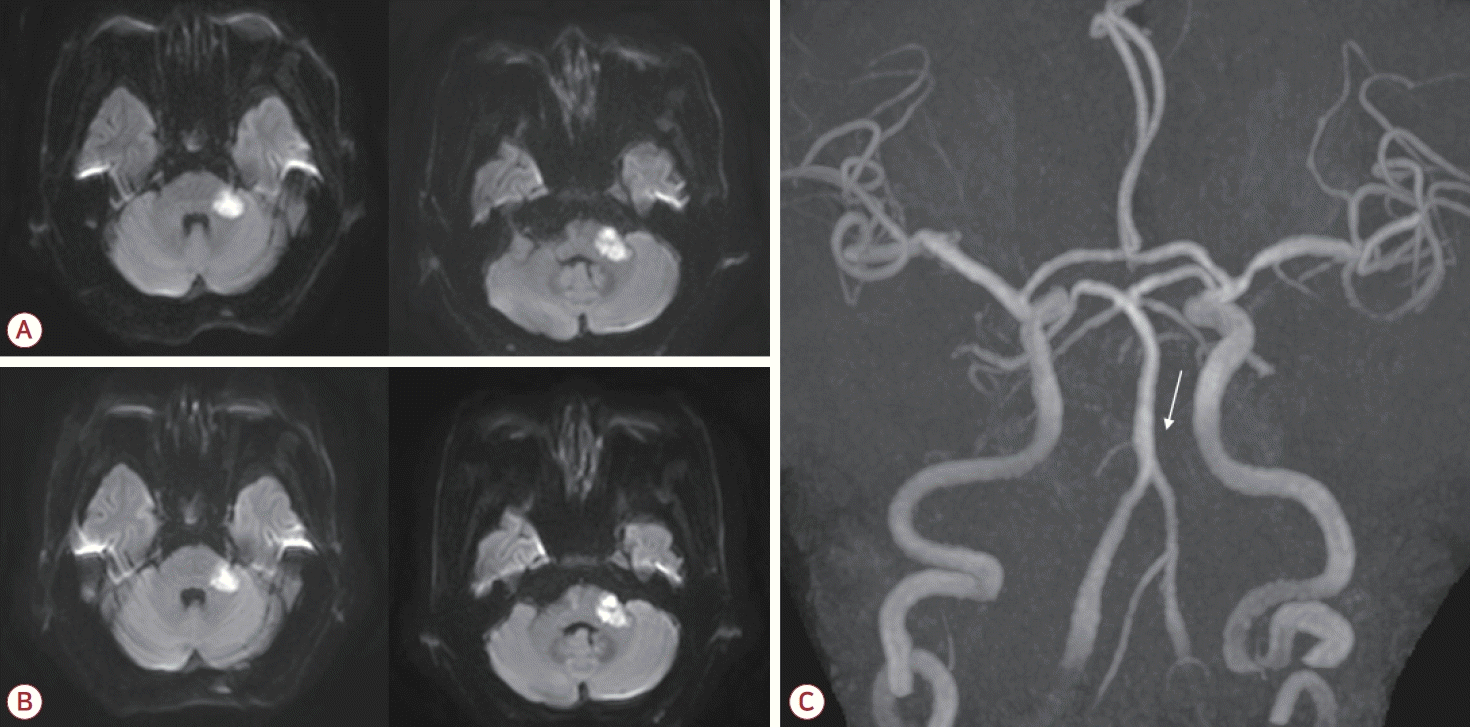

A 76-year-old male was admitted to our hospital due to the sudden onset of dizziness and disequilibrium 7 days previously. His neurological status had deteriorated, and he had been unable to walk independently for the past 5 days. The patient had a history of hypertension that had been managed with medication, and he had no known history of diabetes mellitus, cardiac disease, or previous stroke. In the initial neurological examination the patient was fully alert but had slight dysarthria. Extraocular movements were normal with the exception of gaze-evoked nystagmus being more severe on the left side. Sensations to light touch and pinprick were intact throughout the body, including the face. Despite the patient not complaining of any hearing disturbance, Weber and Rinne tests indicated sensorineural hearing loss on the left side. The muscle strength was normal but the patient displayed bilateral appendicular ataxia, which was more severe in the left limbs. His gait was unsteady and he was unable to walk in tandem. Diffusion-weighted imaging of the brain showed acute ischemic lesions in the left middle cerebellar peduncle and the left lateral pons corresponding to the territory of the AICA (Fig. 1-A). A focal chronic infarction was also observed in the right cerebellum. Magnetic resonance (MR) angiography revealed no abnormalities in the bilateral vertebral arteries or the basilar artery (BA), but there was a cut-off appearance of the left AICA where it originated from the BA (Fig. 1-C). Mild bilateral stenosis was also observed in the mid-M1 segments of the middle cerebral arteries. Hematological and cardiac investigations showed no abnormalities. Measuring the lipid profile revealed total cholesterol at 161 mg/dL, triglycerides at 201 mg/dL, high-density lipoprotein (HDL) cholesterol at 32 mg/dL, and low-density lipoprotein (LDL) cholesterol at 110 mg/dL.

Figure 1.

(A) Diffusion-weighted imaging of the brain showed high signal intensities in the left middle cerebellar peduncle and the lateral pontine area. (B) Follow-up imaging performed 6 days later demonstrated maturation of the ischemic lesions, with no significant expansion. (C) Magnetic resonance angiography of the brain indicated nonvisualization of the left AICA where it originated from the basilar artery (white arrow). AICA; anterior inferior cerebellar artery.

High-intensity statin and dual antiplatelet therapy (aspirin and clopidogrel) was initiated for secondary stroke prevention due to the presence of atherosclerotic risk factors. However, at 3 days after the admission (corresponding to 10 days after the initial onset of stroke symptoms) the patient developed new-onset left facial weakness affecting both the upper and lower face. The weakness had a severity of House-Brackmann grade IV, characterized by an inability to wrinkle the left forehead, incomplete closure of the left eye, and mouth asymmetry (Fig. 2). Ocular movements remained intact. A nerve conduction study of the facial nerves was performed. Following stimulation of the left facial nerve, the compound motor action potentials were 31% lower in the left orbicularis oris and orbicularis oculi than on the right side. After stimulating the left supraorbital nerve, the blink reflex test revealed that ipsilateral R1 and R2 responses were absent while the contralateral R2 response was normal, confirming the presence of left facial neuropathy. The brainstem auditory evoked potential did not respond to the left-ear stimulation. Follow-up magnetic resonance imaging (MRI) of the brain was performed to evaluate the new-onset facial palsy, which revealed maturation of the existing ischemic lesions involving the left middle cerebellar peduncle and the lateral pons (Fig. 1-B). Importantly, no new infarction or significant expansion was detected that could explain the delayed facial palsy. The patient was managed conservatively without corticosteroid therapy, and the left facial palsy improved 1 month after its onset.